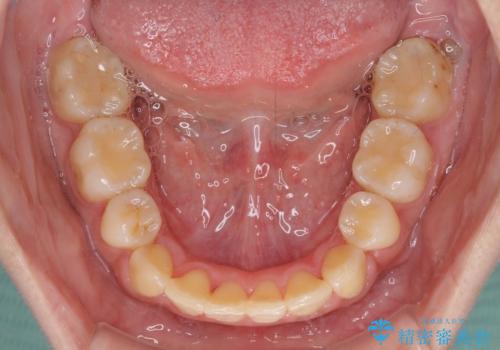

部分矯正で出っ歯になった 出っ歯改善の抜歯矯正

- 上下前歯を部分矯正したところ出っ歯になってしまったとのことで来院された患者様です。

上下左右第一小臼歯4本を抜歯して、積極的に口元を引っ込めるよう、ワイヤー装置にて矯正治療を行うこととしました。